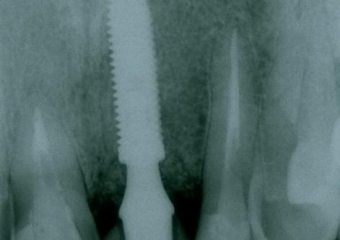

Raio x do dente 21 fraturado

Raio x com prótese provisória fixa sobre implante